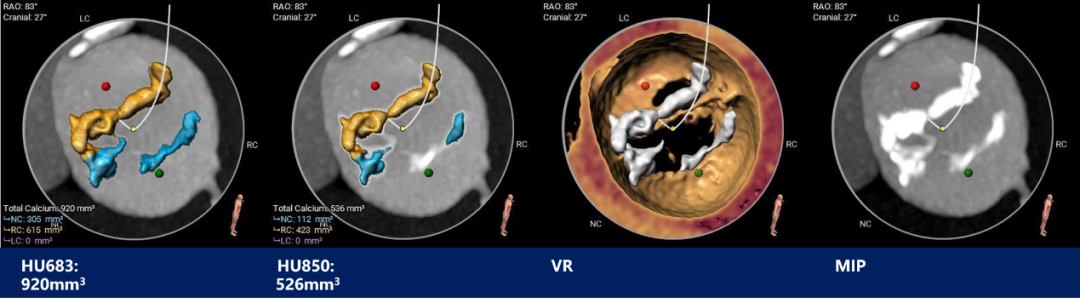

瓣上测量

瓣上测量:瓣叶重度钙化伴增生肥厚,钙化分布不均,主要分布于瓣叶边缘及后壁交界附着缘。